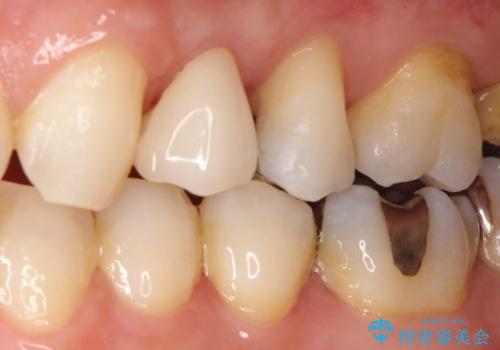

- 歯肉の下まで深く歯が折れたことを主訴に来院された患者様です。

かかりつけ医にて応急的に修復してますが根本的な治療を希望され、矯正的挺出を行ったのち、歯周外科を行い、歯冠修復をしております。

歯肉縁下の水平破折をきちんと治療するためには時間も費用もかかります。